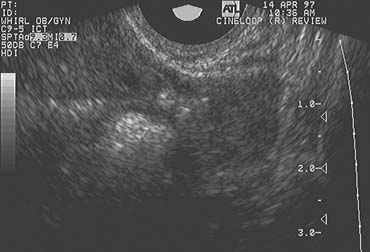

Fig. 2. Images of ovulatory failure. (A) The walls of the unruptured follicle are thin and only marginally luteinized. The antrum contains internal echoes consistent with a filamentous fibrin network. (B) Fully luteinized unruptured follicle. Note the thick, luteinized border surrounding the cloudy blood-filled antrum. The central clot appears to be well organized.

The LUF syndrome is characterized by a preovulatory follicle that grows and develops in a normal pattern but does not collapse at the expected time of ovulation. Ovulation does not, in fact, occur and the oocyte presumably remains trapped within the follicle. The follicular walls subsequently thicken and increase in density much like is seen after a normal ovulation, the follicular margins become less distinct, and the structure persists for the duration of the cycle, regressing in a manner very similar to that of a normally formed corpus luteum (Fig. 3).11,12 Other indices of ovulation (basal body temperature, serum progesterone concentration) remain normal; the time and character of the subsequent menses also are most often entirely normal.